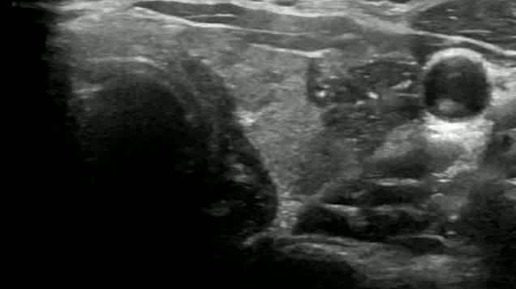

Видео к статье "Стратификация узлов щитовидной железы. TI-RADS-5" https://dzen.ru/a/ZwTJQTbM3zpM5Y6F

Ультразвуковые находки от врача УЗД Зорина Я.П.